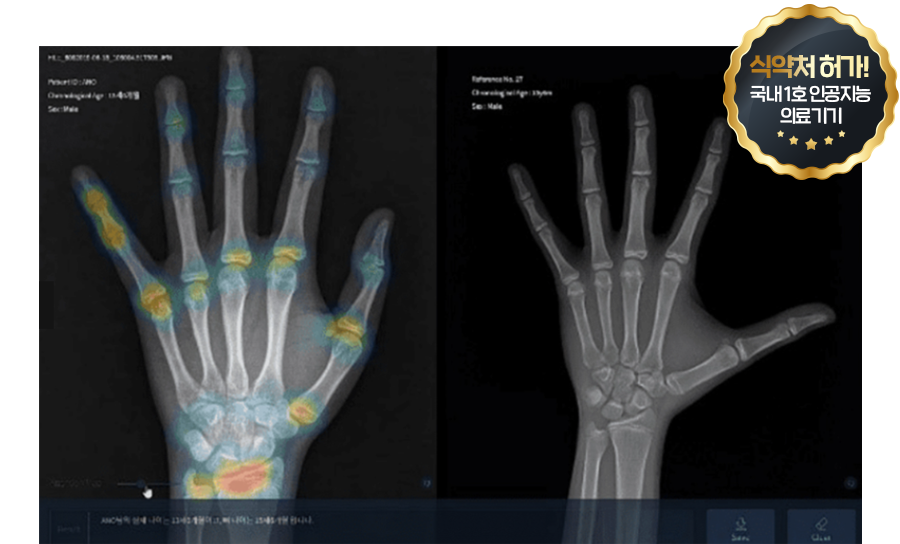

AI 성장 분석으로 더욱 정확하게!

소아/청소년기 환자의 손 엑스레이 영상과 참조표준영상을

비교하면서 수동으로 뼈 나이를 판독하던 것에서 벗어나

인공지능(AI) 기술이 적용된 의료영상분석장치 소프트웨어인

뷰노메드 본에이지(VUNOmed-BoneAge) 장비를 활용하여

엑스레이 영상을 정밀하고 빠르게 판독하여 환자의 뼈 나이를

제시, 정형외과 전문의가 해당 정보를 활용해 성장을 진단합니다.